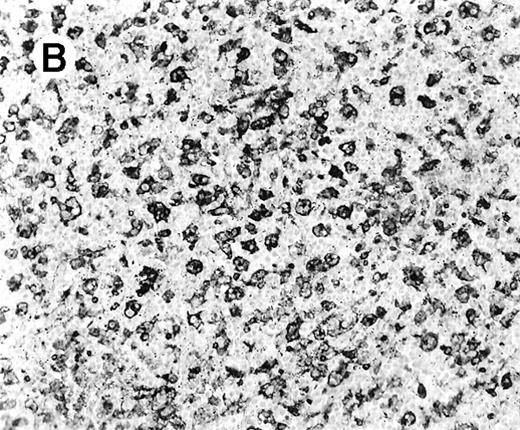

All cases showed essentially similar histologic findings in the liver and spleen. The splenic white pulp was inconspicuous to markedly depleted, whereas the sinusoids showed a prominent lymphoid infiltration (Figure 1A). There was striking hemophagocytosis within the splenic sinusoids (Figure 1B). The infiltrating lymphocytes were small and lacked significant cytologic atypia (Figure 1B). Immunoblasts and plasma cells were not prominent. The liver had prominent portal as well as sinusoidal infiltrates of small lymphocytes morphologically identical to those noted in the spleen (Figure 2). There was intracellular and intracanalicular cholestasis, steatosis, and focal necrosis. Hemophagocytosis was present within the sinusoids. In case 5, the spleen showed extensive areas of necrosis mainly in the perifollicular and periarteriolar lymphoid sheaths of the white pulp with the presence of immunoblasts reminiscent of IM.

Histologic findings in spleen.

(A) Section of spleen from case 2 shows depletion of white pulp and prominent sinusoidal small lymphoid infiltrates (hematoxylin and eosin, × 200). (B) The lymphocytes lack significant cytologic atypia. There is marked hemophagocytosis (hematoxylin and eosin, × 600).